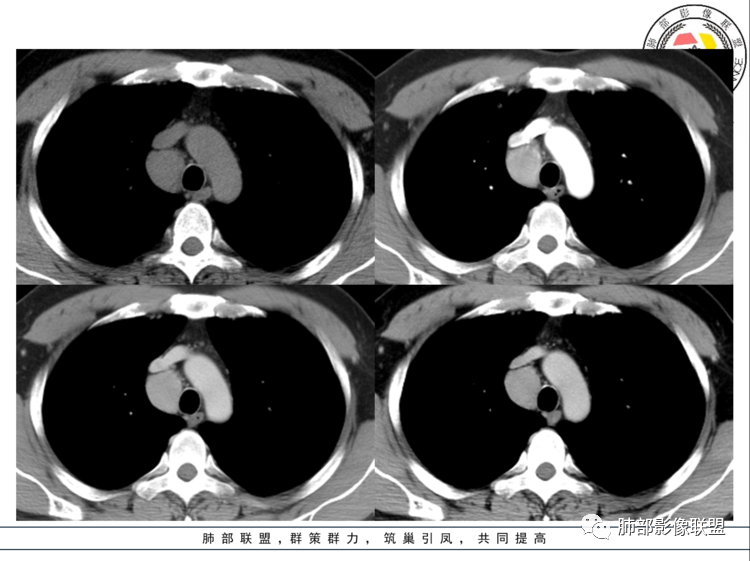

男,40岁,体检发现纵隔占位

•查血常规、血生化、肿瘤标志物、尿常规大致正常。气管腔静脉间隙团块状影,密度均匀,边界清楚,增强扫描,明显的强化,肿块的周围气管旁见多个肿大的淋巴结,强化特点类似。考虑良性占位,巨淋巴增生症。需要与异位胸腺瘤、结节病、淋巴瘤、副神经节瘤、淋巴结转移瘤鉴别。

气管腔静脉间隙淋巴结增大,边界清,密度均匀,明显均匀强化,周围有小淋巴结,考虑巨淋巴结增生症。

病灶位于气管腔静脉间隙淋巴结增大,边界清,密度均匀,动脉期明显均匀强化,有小血管进入,周围有小淋巴结,考虑巨淋巴结增生症CD,鉴别诊断:神经鞘瘤

右上前中纵隔占位,上腔静脉后方,血管无推移,边缘光滑,密度均匀,上下跨度较大成长条,动脉期明显强化,考虑巨淋巴结增生症CD。鉴别神经源性肿瘤,支气管囊肿。

男,40岁,体检发现纵隔占位,查血常规、血生化、肿瘤标志物、尿常规大致正常。CT示纵隔占位,边缘光滑,周围可见小淋巴结影,强化动脉期明显强化,考虑CD可能

前纵隔右侧气管旁可见软组织密度肿块影,大致圆形,密度均匀,边缘清晰规整,周围脂肪间隙存在,增强明显强化。考虑良性占位,首选CD。鉴别神经源性肿瘤。